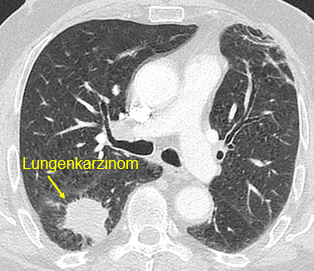

Beispielhafte Aufnahmen verschiedener Erkrankungen

(Lungenklinik Lostau)

Lungenkrebs – Diagnostik, Verlauf und interdisziplinäre Abstimmung

Die Computertomographie (CT) ist die zentrale Untersuchung bei Verdacht auf Lungenkrebs, zur Stadieneinteilung und Verlaufsbeurteilung sowie für die Therapieplanung. Bei auffälligen Befunden wird das weitere Vorgehen interdisziplinär abgestimmt. Weitere Informationen finden sie außerdem auf den Seiten unseres Lungenkrebszentrums.